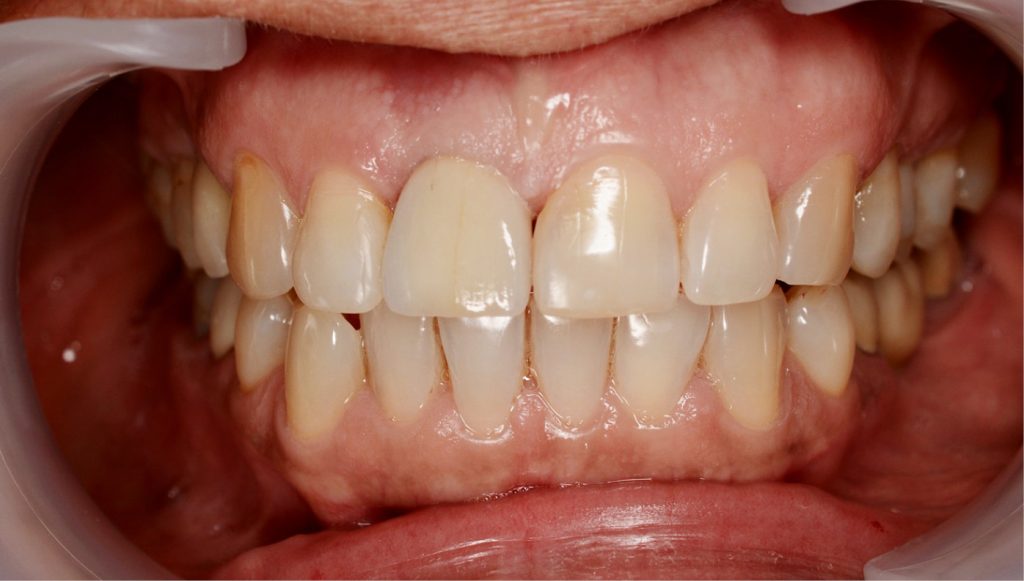

STRESZCZENIE: Rehabilitacja protetyczna z użyciem implantów w strefie estetycznej jest jednym z najbardziej wymagających zadań w stomatologii implantologicznej. Uzyskanie optymalnego efektu estetycznego stawia przed lekarzem klinicystą ogromne wyzwanie. Stworzenie atrakcyjnej odbudowy implantologicznej w strefie estetycznej opiera się na szczegółowym planie leczenia. Wynik estetyczny zależy od aspektów chirurgicznych i protetycznych. Aspekty chirurgiczne obejmują prawidłowe ułożenie platformy implantu w trzech kierunkach i udane zachowanie lub odtworzenie ściany kości przedsionkowej o odpowiedniej wysokości i grubości. Aspekty protetyczne obejmują jakość samego uzupełnienia oraz tworzenie otaczających je tkanek miękkich okołoimplantacyjnych, czyli profilu wyłaniania, które harmonizują z sąsiadującym uzębieniem.

SUMMARY: Prosthodontic rehabilitation with implants in the aesthetic zone is one of the most demanding tasks in implant dentistry. Obtaining an optimal aesthetic effect poses a great challenge to a clinician. Creating an attractive implant reconstruction in the aesthetic zone is based on a detailed treatment plan. The aesthetic result depends [...]